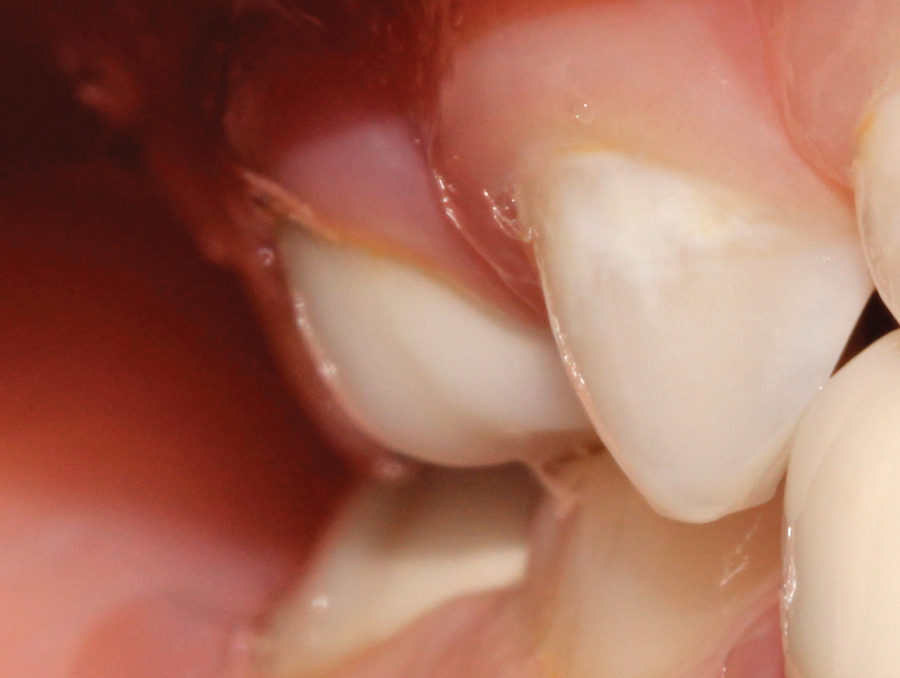

Figure B. After orthodontic treatment. Note hyperplasia of gingival secondary to anti-seizure medication

One of the foundations upon which health care professionals practice is a commitment to provide the best possible treatment to each and every one of their patients. For some patients, medical or socioeconomic circumstances may present a challenge to the delivery of optimal care. Fortunately, we live and practice in a country that provides an … Read more